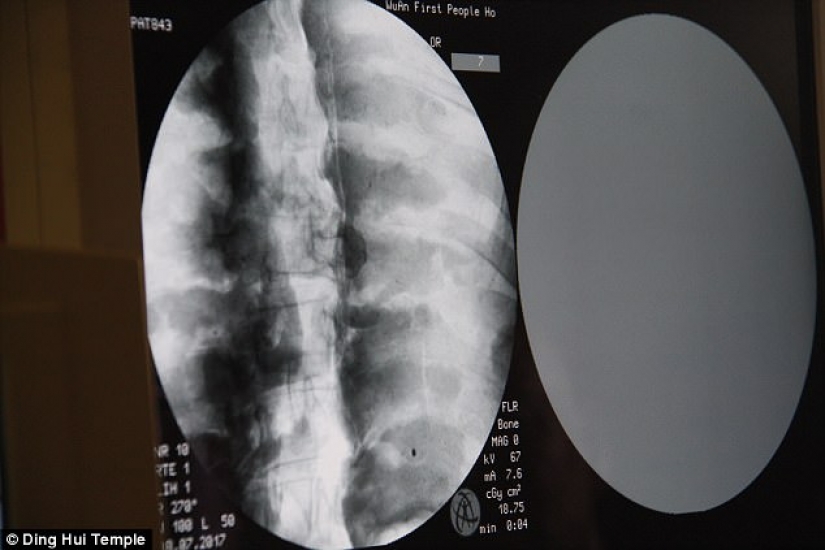

By Pictolic https://www.pictolic.com/article/a-thousand-year-old-mummy-of-a-buddhist-monk-has-a-brain-and-skeleton-preserved-in-perfect-condition.htmlThe mummified body of a thousand-year-old Buddhist monk still has the bones and brain intact. This was revealed by a CT scan.

The CT scan was performed on July 8. People were shocked when the doctors said that Ci Xian's skeleton and brain were in perfect condition. "We can see that his bones are as healthy as a normal person's. The upper jaw, upper teeth, ribs, spine, and all joints are perfectly preserved. This is incredible, " said Dr. Wu Yongqing.